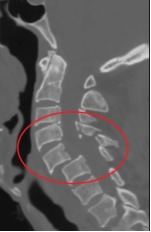

高龄复杂病例来院 3月8日晚,我院急诊科通知骨科值班医师黄孝明接诊一位来自甘孜色达高龄患者:79岁,男,藏族,外伤8天,右上肢肌力2-级,右下肢完全瘫痪家中卧床8天,颈托固定,大小便失禁,消瘦,急诊颈椎CT检查显示“颈椎多发骨折(C4-6)伴脱位C5/C6”,初步判断合并颈部脊髓损伤,需手术治疗。因手术难度超出当班医生能力范围,请示骨科主任医师吴俊一后,经综合评估患者病情及我院技术水平,为稳妥起见,决定两种方案,一是邀请骨科专科联盟单位(四川省人民医院)脊柱外科张伟教授来院手术,二是患者上转至省医院。充分告知患者及家属两种方案利弊,征得其同意并选择专家来我院诊治及手术。

全力做好术前准备。患者入住骨科后,颈椎核磁共振证实“颈部脊髓损伤(颈4-6平面)、颈椎硬脊膜血肿(颈5、6平面)”。因合并“胸7椎体压缩骨折、左侧多支肋骨骨折(2、6、7)、胸骨骨折、肺部感染、高血压病、低钠血症”,且存在压疮、深静脉血栓等高危因素,病情复杂且危重,骨科医护团队第一时间启动心血管内科、麻醉科等多学科MDT联合会诊,积极完善术前检查、防治肺部感染、压疮、深静脉血栓、关节僵硬、营养不良等并发症,力争将患者身体状态调整到尽可能安全水平的。